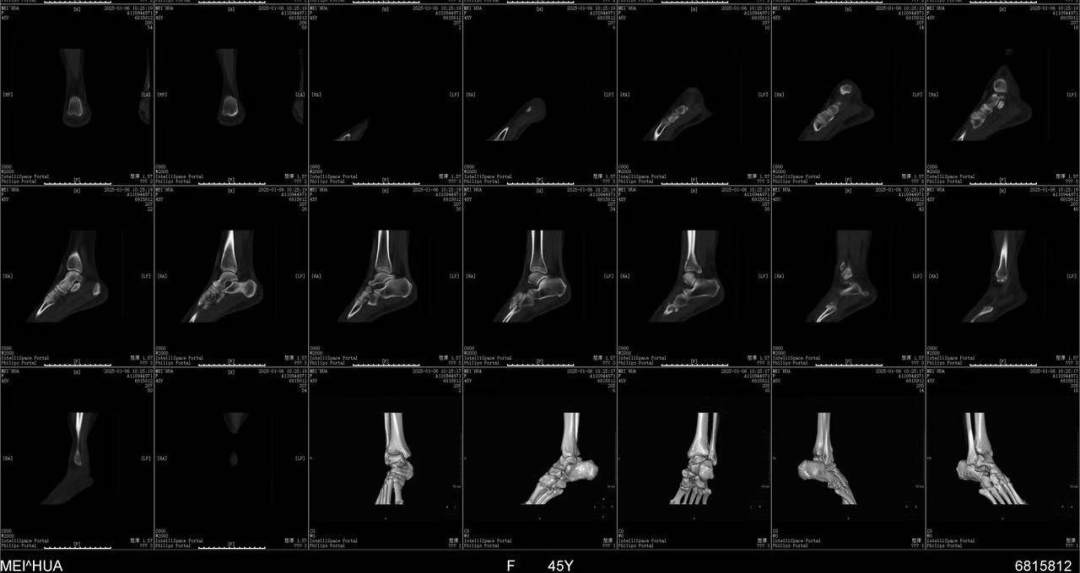

患者: 女性,45岁 -

初诊日期: 2025年1月25日

患者主诉其右踝于2024年12月15日下楼梯时摔倒受伤,随后进行了石膏固定,并一直采取保守治疗至今。目前使用拐杖+行走靴辅助行走,下台阶时外踝疼痛。 -

客观检查 (初诊及后续随访)

膝关节主动活动度 (AROM):

屈曲:左(L) 140度 / 右(R) 137度

过伸:左(L) +5度 / 右(R) +5度 -

踝关节8字维度测量/Figure 8 Measurement Test

左(L):47厘米 (2025年2月16日)

右(R):44厘米 (2025年1月25日) → 47厘米 (2025年2月5日) → 46厘米 (2025年2月9日) → 45厘米 (2025年2月16日) -

膝关节扭矩力量 (KTW – Knee To Wall):

左(L):16厘米

右(R):9厘米 (2025年1月25日,因患者恐惧及拒绝,推迟测量) → 4厘米 (2025年2月5日) → 8厘米(2025年2月9日) → 8厘米(2025年2月16日)

踝关节及第一跖趾关节 (1st MTR) 活动度受限,患者抗拒跖屈。

踝关节特殊测试: 均为阴性。

触诊: 足底筋膜紧张;小腿三头肌萎缩伴胫骨后肌压痛;跟骨和距骨活动受限。